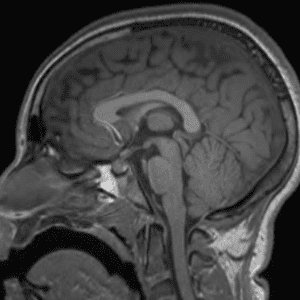

Brain Tumor Practice Cases

Case #2

Cavernous malformation